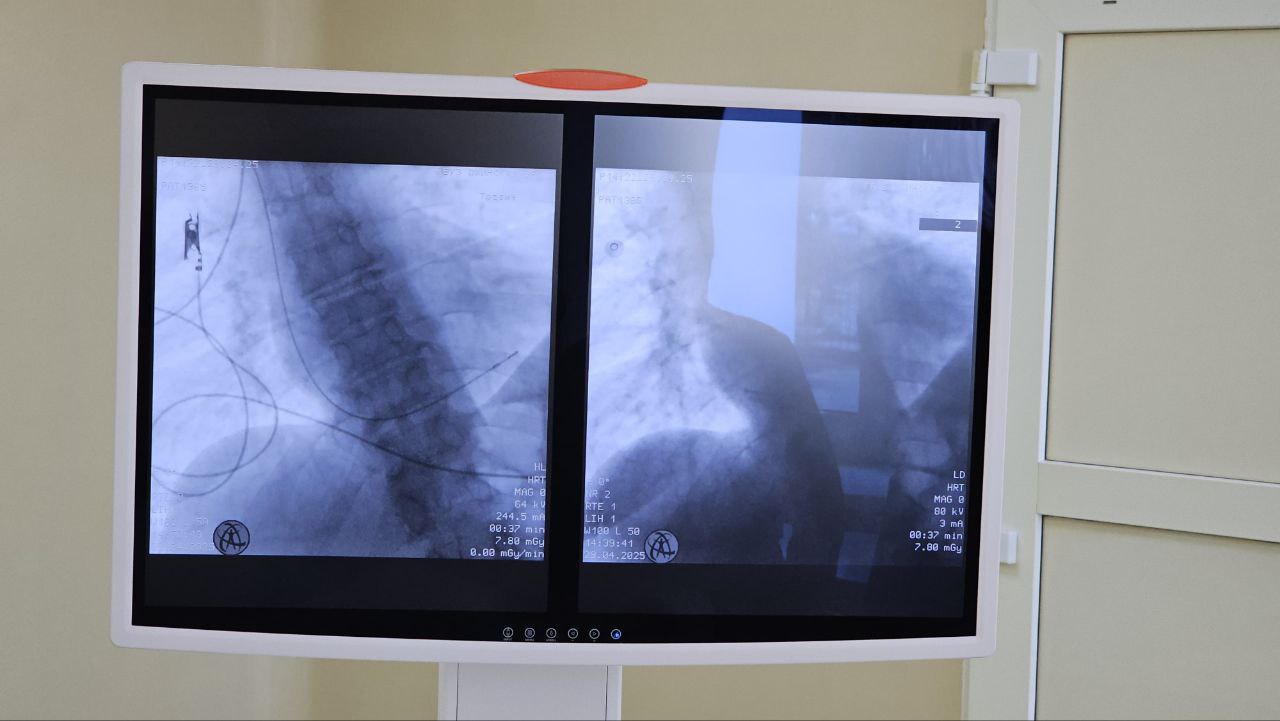

В Охинской ЦРБ впервые проведена манипуляция по установке электрокардиостимулятора с помощью С-дуги. Благодаря современному оборудованию врачи смогли оперативно стабилизировать состояние пациентки и тем самым спасли ей жизнь.

— В первичное сосудистое отделение жительница Охи поступила с жизнеугрожающим нарушением сердечного ритма 29 апреля. Для поддержания сердцебиения женщине требовалась экстренная установка электрокардиостимулятора. Специалисты приняли решение проводить имплантацию прибора под контролем С-дуги. Для нашей больницы это был первый опыт использования электронно-оптического преобразователя в кардиологии. Операция прошла успешно, — рассказывает Николай Рубанов, главный врач Охинской ЦРБ.

Провел операцию заведующий первичным сосудистым отделением Денис Кенджиев при участии заведующей кардиологическим отделением Людмилы Рубановой и врача-травматолога Артема Любых. Вся манипуляция заняла у докторов не больше 20 минут, что полностью отвечает действующим стандартам оказания медицинской помощи. Ранее установка временных электрокардиостимуляторов проводилась в райцентре «по старинке». Без объективного визуального контроля, который дает С-дуга, операции могли длиться до двух часов, из-за чего был выше риск возникновения осложнений.

— Установка временного электрокардиостимулятора – экстренная инвазивная операция, которая проводится при жизнеугрожающих нарушениях сердечного ритма. Прибор помогает сердцу биться с нужной частотой, вне зависимости от того, способно ли оно само работать правильно. Благодаря С-дуге наша пациентка находилась на операционном столе минимальное количество времени. Женщина уже направлена в региональный сосудистый центр для оперативного лечения ее сердечной патологии. С электрокардиостимулятором до областного центра она добралась в безопасном для жизни состоянии, — отмечает Денис Кенджиев.